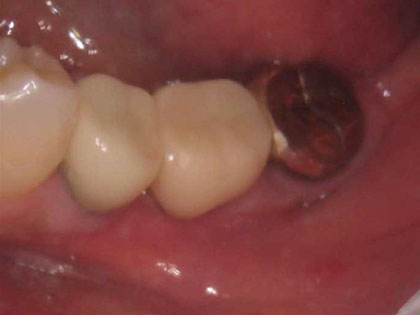

何度も腫れや痛みを繰り返してきたとの事で来院された患者様の症例になります

初診時のレントゲン写真がこちら

症例

50代女性

主訴

何度も腫れや痛みを繰り返してきた

治療期間

4か月(外科的治療は1日、経過観察は4か月)

治療回数

治療内容

再生療法、リグロス

治療費用

保険

治療経緯

術前レントゲンの5番目、6番目の歯根間

6番目の分岐部(根本部分)の所が黒く抜けています

骨がとけています。